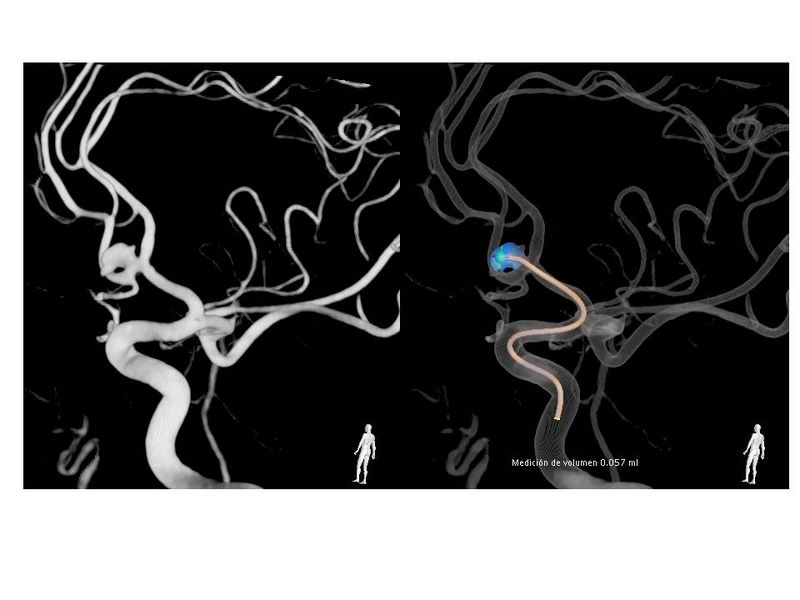

Aneurismas